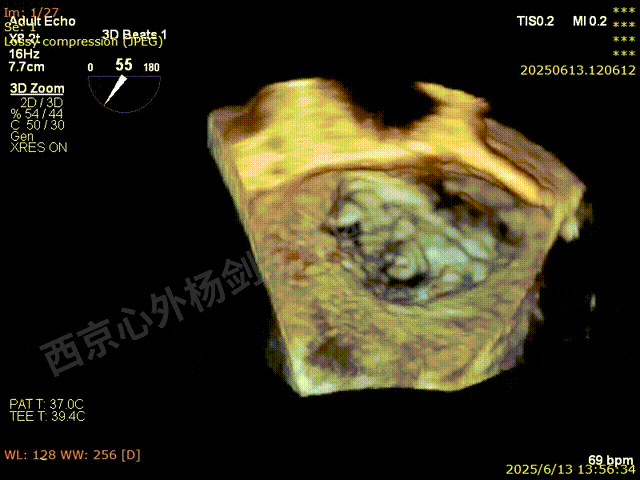

TEER术前超声评估

二尖瓣后叶栓系严重,前叶相对错位,反流束沿2区分布广泛,2偏3区处存在反流。

反流宽度至少23mm,因影像调整困难,考虑实际反流更宽。

术前3D数字模型

TEER手术难点

1、心脏过大,术中影像标准切面难以获取,TEE引导难度较大。

2、后叶大片栓系,栓系严重至8点钟,反流宽度较宽,α角度大,捕捞困难。